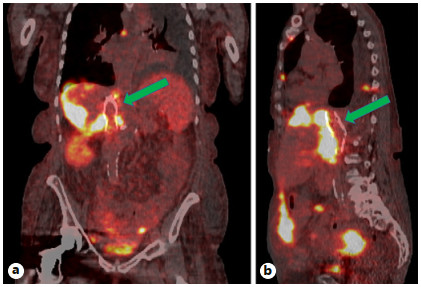

Abstract: Small bowel-origin carcinoid tumor is indolent but may metastasize relentlessly to various sites, including the liver. Over the past 9 years, we have treated a 69-year-old woman who has undergone 5 percutaneous liver ablations, 5 hepatic intra-arterial chemoembolizations, an ovarian cryoablation, and a trans-ventral hernia mesenteric cryoablation. These interventions are all related to her inoperable carcinoid malignancy. After the patient presented with swelling of the abdomen and both lower extremities, computed tomography (CT) angiography was performed, revealing a circumferential hepatic metastatic mass encasing the intrahepatic inferior vena cava (IVC) and extensive third spacing of fluids specific to the IVC distribution below the diaphragm. A venogram of the intrahepatic IVC revealed extrinsic compression causing 95% narrowing of the vessel. A balloon was advanced to the level of the lesion and inflated, increasing the caliber of the vessel. Subsequently, 2 covered aortic stent graft cuffs were deployed in an overlapping fashion within the lumen of the IVC, traversing the area of narrowing. Next, an open-cell aortic dissection stent was placed across both overlapping aortic stents from the renal veins to the hepatic veins. Following this, three 17-gauge cryoablation probes were inserted into the segment 1 intrahepatic lesions encasing the newly stented IVC via an anterior percutaneous approach. Two 10-min freeze cycles were performed with intraoperative CT imaging, demonstrating circumferential coverage of the lesions. Posttreatment venogram revealed patent stent grafts within the intrahepatic IVC, and restoration of vessel patency. No immediate postoperative complications were noted. The patient’s abdominal and lower extremity swelling resolved completely within 1 week after procedure. Two-month follow-up CT demonstrated markedly decreased size of the metastatic lesions and no adverse effects. Six- and 9-month PET-CT scans demonstrated maintained patency of the IVC stent. This palliative procedure allowed the patient to maintain good performance status and alleviated her symptoms of IVC syndrome. The radial force generated by the multiple aortic stents will ostensibly maintain the patency of the intrahepatic IVC. Cryoablation of the encasing metastatic lesion was performed with markedly decreased size of the tumor on the 2-month follow-up.